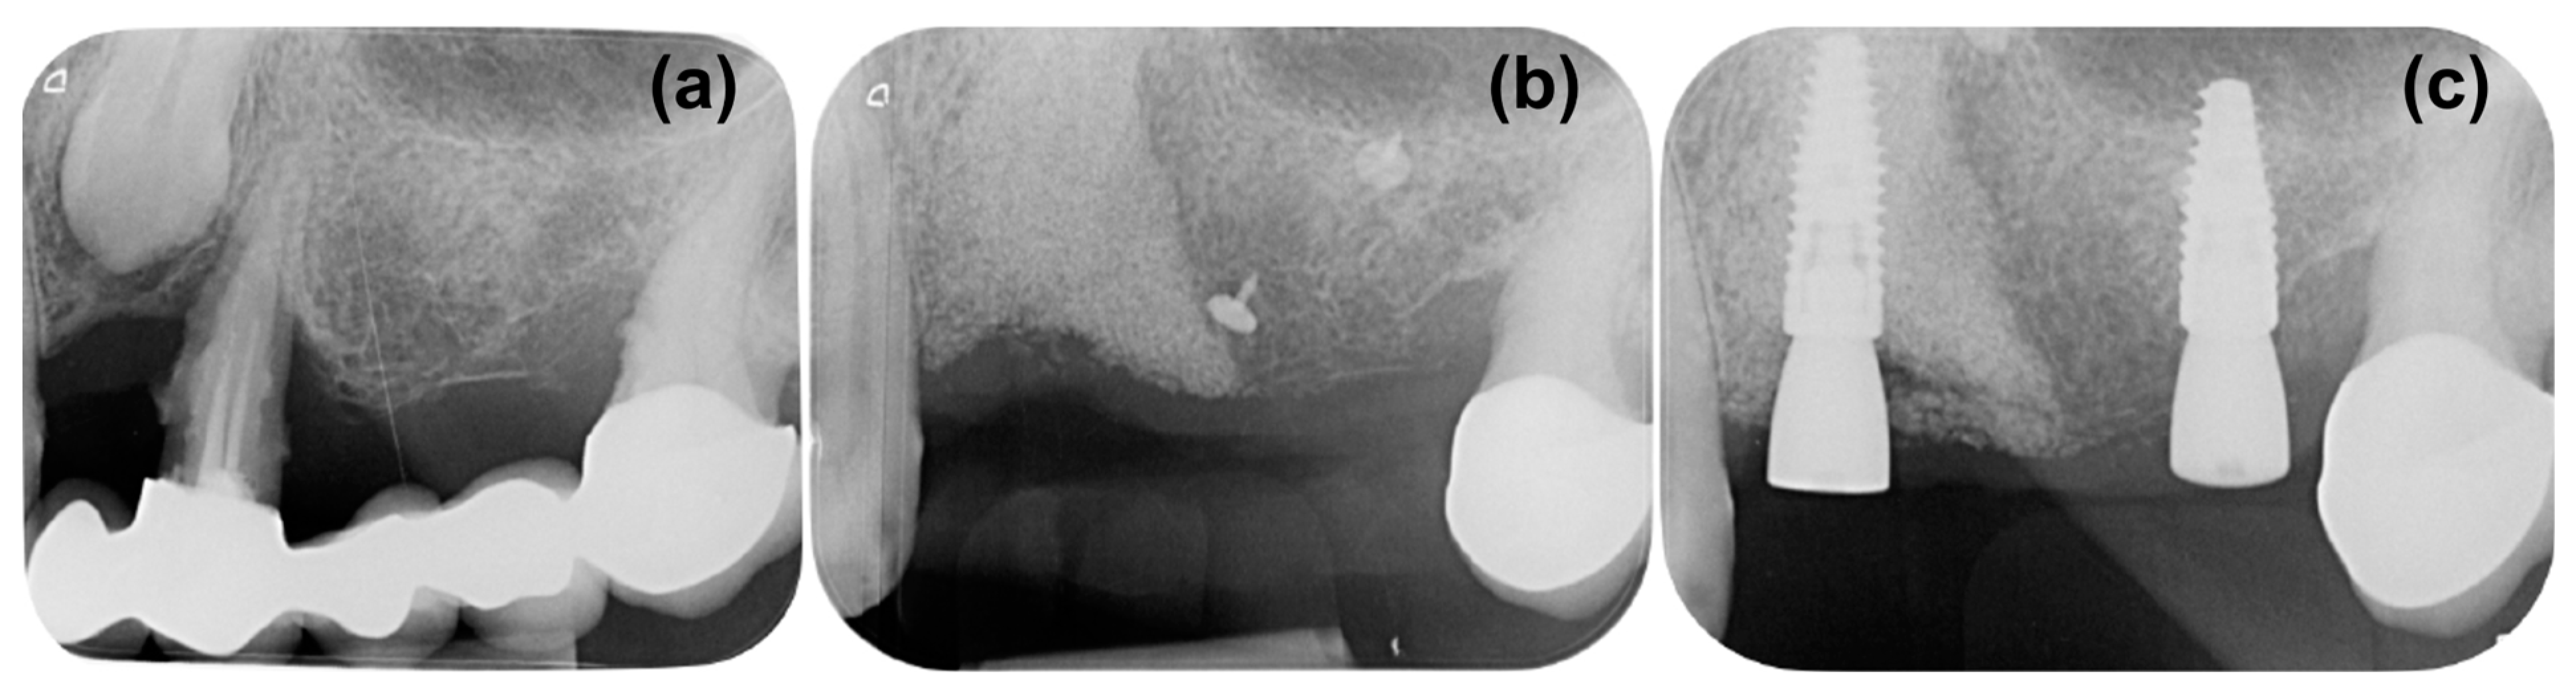

It was determined that additional support would be necessary to maintain the bone volume in the augmented defect. Using a magnesium membrane, a resorbable supporting arch was built over the augmented bone, stabilizing the graft. The mechanical stability of the membrane was intended to resist the compressive forces of the overlying soft tissue to provide the maximum volume for new bone to grow into and occupy [42]. The mechanical support that can be provided by the magnesium membrane has previously been demonstrated by Elad et al. [26], who used the membrane to bridge the buccal or palatal walls in compromised sockets. Using the membrane in this method supported the graft and therefore preserved the ridge height during the healing period. It was also reported that there was a formation of a cortical plate in the position of the augmented bone. The mechanical stability of the magnesium membrane was also demonstrated in the presented clinical case, as it provided a stable structure that enabled new bone to grow both horizontally and vertically into the defect space (Figure 6a,b). The bone volume was preserved during the extended healing period, after which the placement of two dental implants into the augmented bone was possible.

Figure 6.

Comparison of periapical X-rays during different phases of the treatment, (a) the initial situation, (b) control X-ray at 8 months, prior to reentry, (c) post operative X-ray after implant placement.